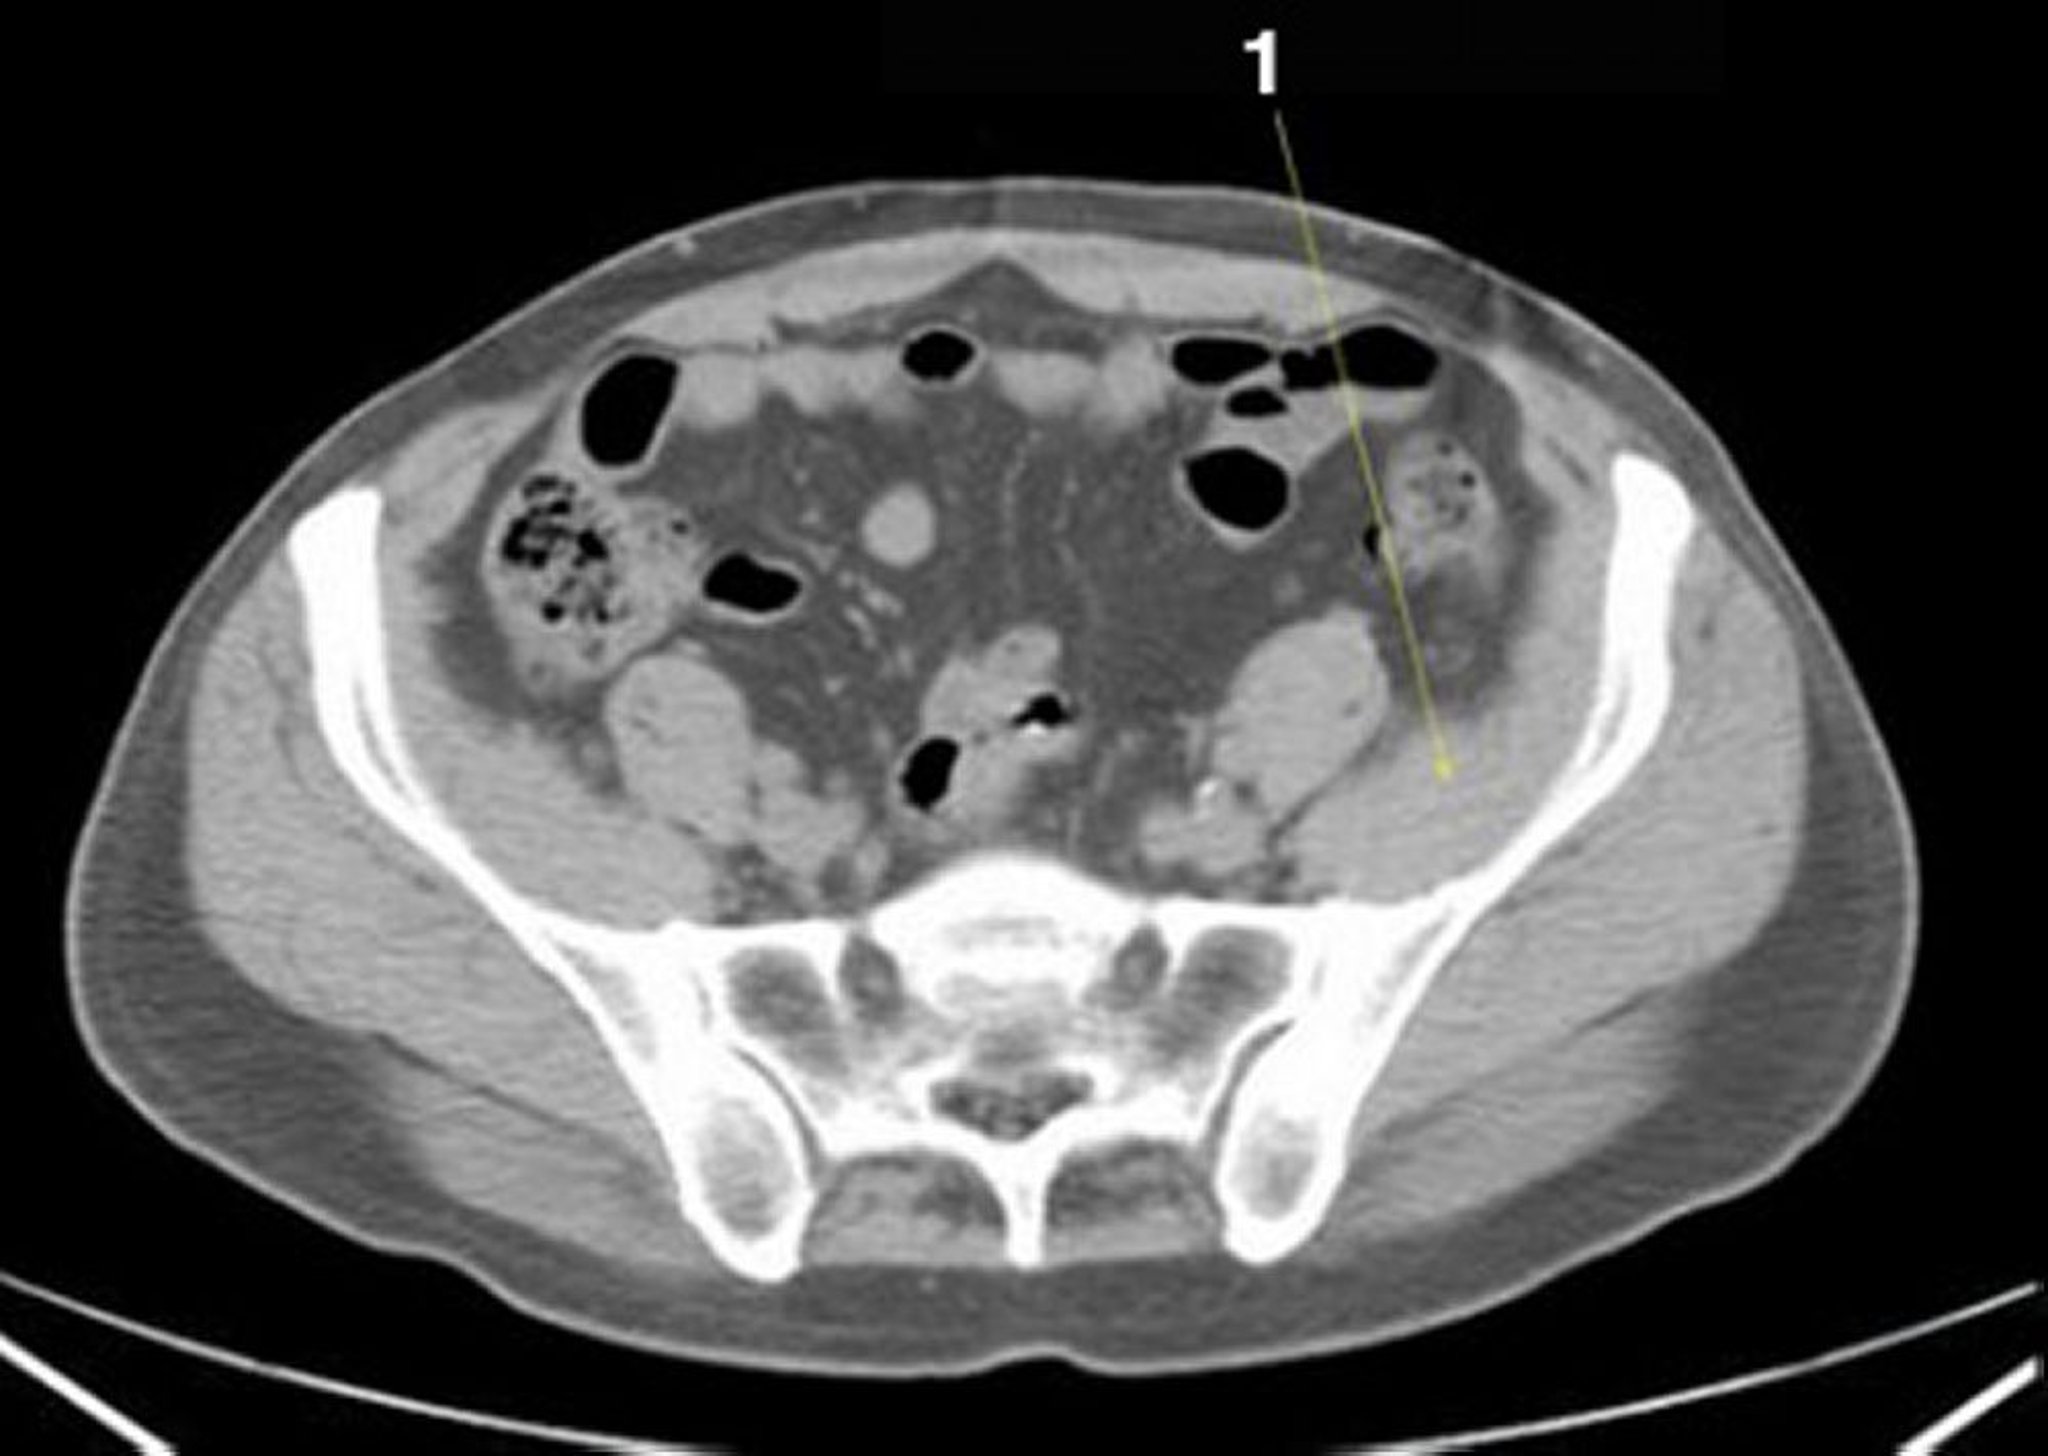

Noncontrast CT Scan of the Abdomen and Pelvis Showing Normal Anatomy (Slide 22)

1 = iliacus muscle.